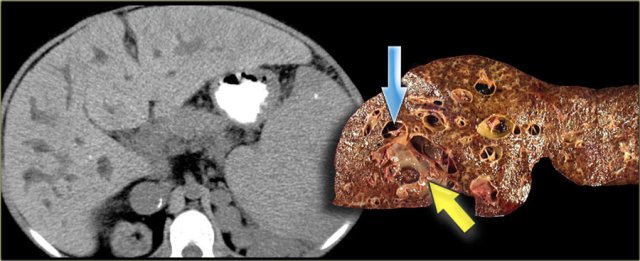

The patient on the left developed severe liver failure and a resection was performed.

Notice the intrahepatic bile duct dilatation, splenomegaly and dilated venous collaterals.

In the resected specimen there is a central dot sign (blue arrow) and a small pus collection (yellow arrow).

Cholangiocarcinoma can take on many forms in patients with Caroli disease.

The cholangiogram on the left demonstrates a focal stricture (blue arrow), which turned out to be a infiltrating cholangiocarcinoma.

The patient on the right has a cholangiocarcinoma in which the tumor was filling up the dilated ducts (yellow arrow).